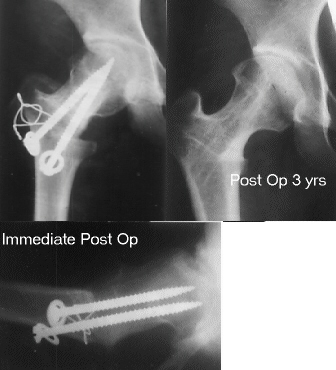

The large posterior surface of the femoral head remained intact, therefore she is a good candidate for a Sugioka osteotomy. A Sugioka osteotomy was performed with 90 degrees of anterior rotation and 15 degrees of varus angulation. After post-operative non-weight-bearing for 4 weeks, and partial-weight-bearing for 6 weeks, she has had neither limping nor pain so far.